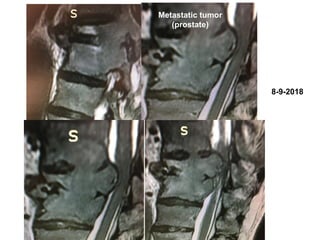

8-9-2018

Metastatic tumor

(prostate)

Spinal cord

decompresion

and

percutaneous

spondylodesia